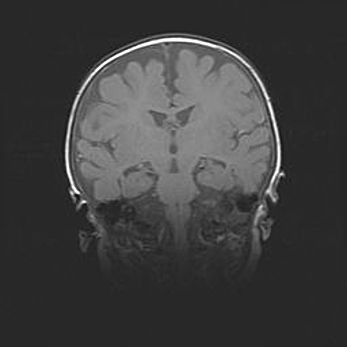

Открытая гидроцефалия.

Возраст: 9 месяцев 12 дней

Вес: 6800 г

Пол: мужской

Окружность головы: 41,5 см

Срок гестации: 28 недель

Гидроцефалия головного мозга у новорожденных имеет характерный признак: опережающий рост окружности головы приводит к визуально хорошо определяемой гидроцефальной форме сильно увеличенного в объёме черепа. Детские неврологи определяют следующие симптомы гидроцефалии у грудничков: выбухающий напряжённый родничок, частое запрокидывание головы, смещение глазных яблок к низу.